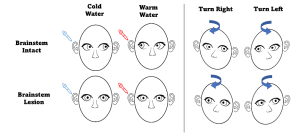

Vestibulo-ocular Reflex

Oculocephalic reflex (Doll’s Eye maneuvers)

Before proceeding with this test, ensure that the patient has a stable cervical spine. During the test, the patient’s eyelids are held open, and the head is briskly rotated from side to side. It is important to rotate fast enough to overcome pursuit. A positive reflex is seen when there is conjugate eye movement in the opposite direction of head rotation, with a gradual return to midline position.[11] This positive finding demonstrates that CN III, VI, VIII, corresponding nuclei in the midbrain/pons, and the vestibular system are intact bilaterally. A negative finding, as seen with eyes in the midline position moving in the same direction as head rotation, similar to a doll’s eyes, suggests brainstem dysfunction from the level of the midbrain to the pons.[18]

Caloric Testing Before proceeding with this test, ensure the patient has an intact tympanic membrane. A small amount of fluid (water or air), either 7oC over (warm) or 7oC under (cold) the bodily temperature, is flushed into one of the ear canals. A positive finding will show conjugate horizontal nystagmus; however, the direction of the nystagmus is dependent on the relative temperature of the fluid. Warm fluid will cause the fast phase of nystagmus to be towards the irrigated ear, while cold fluid will cause the fast phase to be away from the irrigated ear.[19] One study showed that a positive finding in a comatose patient is a strong predictor (PPV=0.93) for emergence from a vegetative state.[20] Another study showed that the absence of a vestibulo-ocular reflex predicted 100% of cerebral death.[21] Similar to the oculocephalic reflex, a negative finding indicates a deep metabolic coma, vestibular damage, or brainstem dysfunction from the level of the midbrain to the pons.